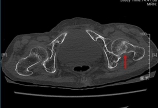

男,86岁,166cm,48kg,左髋疼痛并活动受限12天,高血压20年,冠状动脉性心脏病20年,否认骨折史,吸烟史50余年,否认激素应用史专科查体:视诊:左下肢外旋60°畸形,肌肉萎缩触诊:左腹股沟中点压痛,大转子叩痛动诊:左髋活动疼痛量诊:屈60°,伸0°,内旋10°,外旋20°内收0°,外展15°特殊检查:“4”字试验(+),Thomas sign(-)辅助检查:骨盆CT:股骨颈骨折